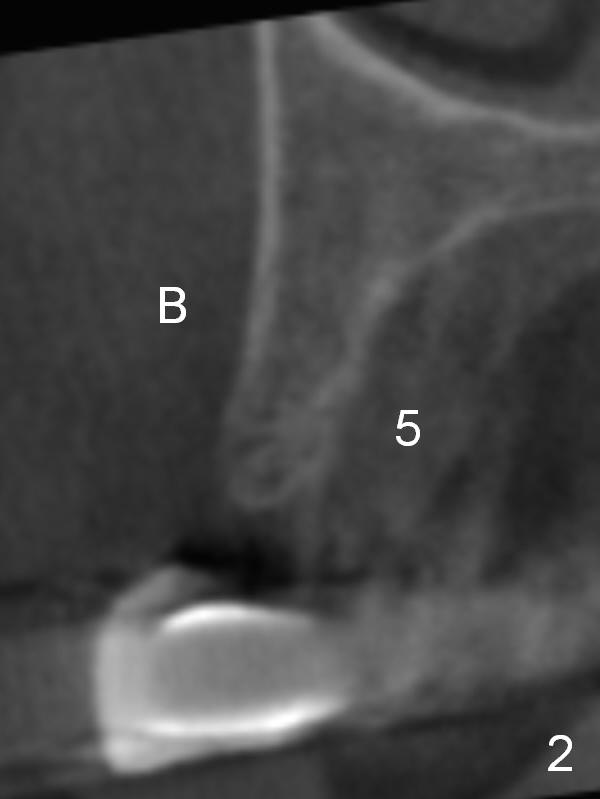

CT scan taken 10 days post immediate implant placement at #3, 4, and 10 shows that the edentulous area is narrow (Fig.1 (axial section), 2-6 (coronal sections; B: buccal)). In addition, the bone density is 100-200 Hounsfield units (Fig.2). Osteotomy should be underprep: 1.2 mm to the depth; 1.5 mm haft the depth. It appears that 2.5 or 3.0 mm 1-piece implants can be placed at #5,7 and 8 (Fig.3,5,6). Check buccopalatal trajectory after each step of osteotomy using surgical stent. Insert a 3 mm dummy implant tentatively. If it looks too wide for the ridge, use a 2.5 mm implant. If trajectory is off, use an angled one, especially at #7 (Fig.5).